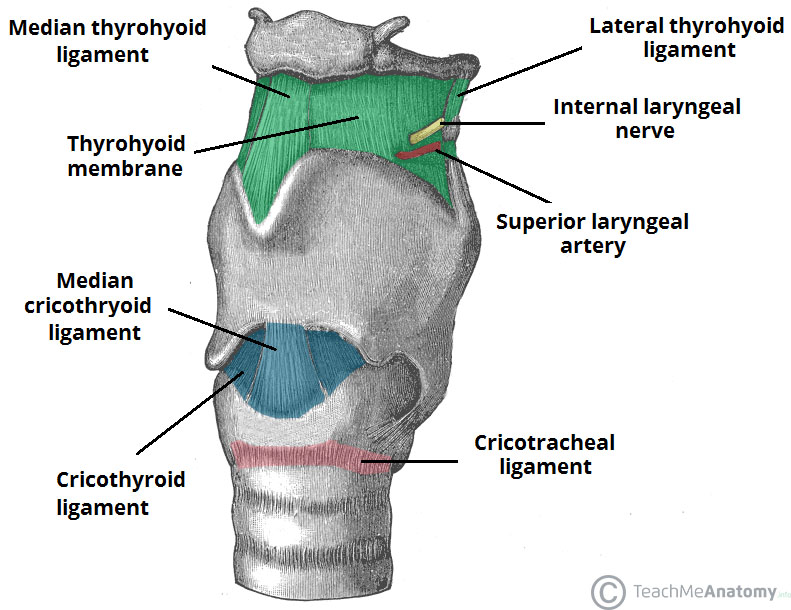

Larynx

Artery

Nerve

- Sup. laryngeal n.

- Internal br.(Internal laryngeal n.)

- Sensor

- 穿過 Thyrohyoid ligament

- External br.

- Motor

- Internal br.(Internal laryngeal n.)

- Recurrent laryngeal n.

- Inf. laryngeal a.伴行

- 過Cricothyroid joint改叫Inf. laryngeal n.